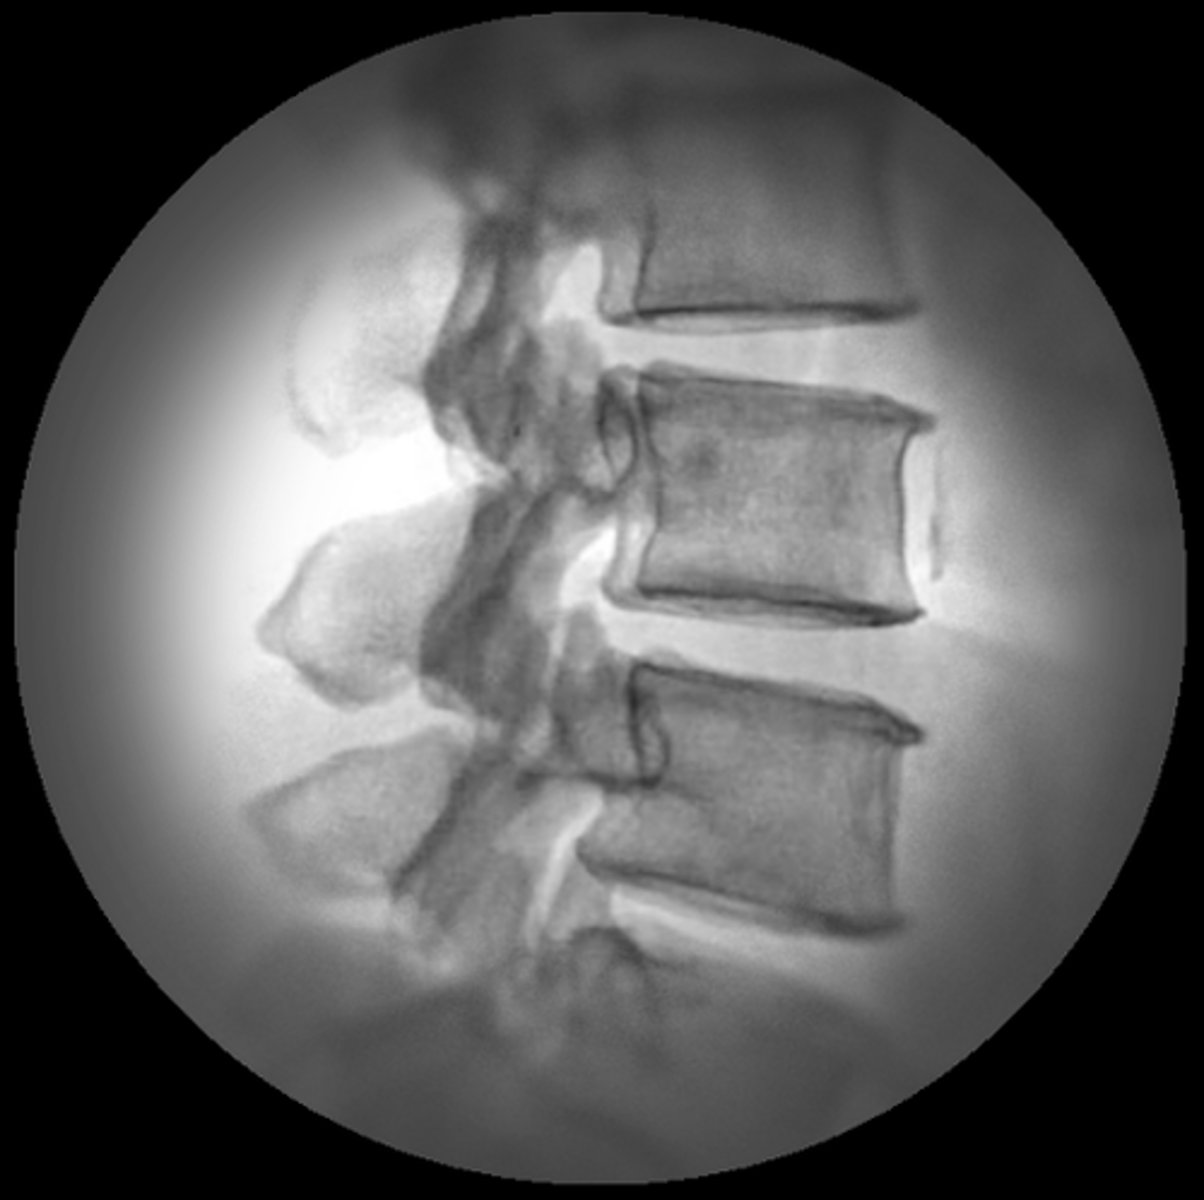

Which of the following terms is often used to describe fluoroscopy imaging?

c. Dynamic